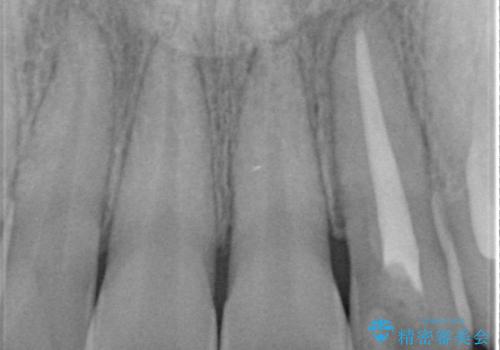

- 前歯の変色を主訴に来院されました。

根管治療後、オールセラミッククラウン(エクセレント)にて治療を行なっています。